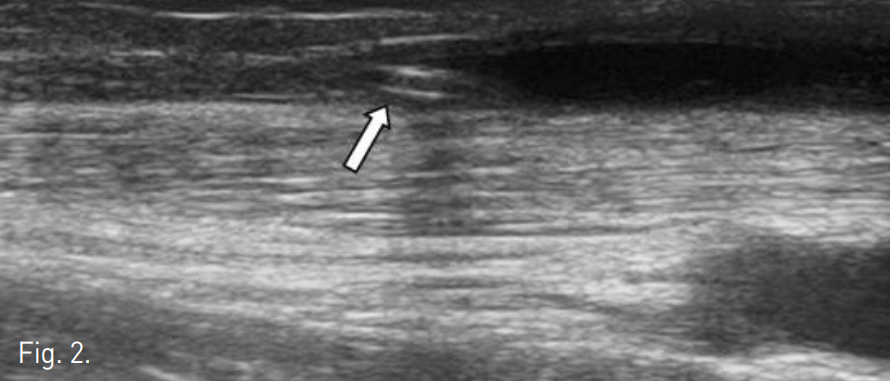

초음파 유도 하에 협착된 부위의 상부의 cephalic vein 을 천자하고 7F Sheath 를 삽입하였다. 5F KMP catheter (Cook, Bloominton, USA)를 이용하여 fistulography를 시행하여 distal cephalic vein 의 total occlusion 을 확인하였다. 초음파 유도 하에 5F KMP catheter를 occlusion 부위의 입구에 wedging 시키고(Fig. 2), 0.035" guidewire (Radiofocus, Terumo, Japan)를 이용하여 U-loop를 형성하여 동맥폐색의 재개통술에서 이용하는 subintimal dissection과 같은 방법으로 폐색부위를 통과하였다

Fig. 2

A KMP catheter is introduced proximally to the occlusion. The tip of the catheter is positioned abutting the occlusion (arrow).